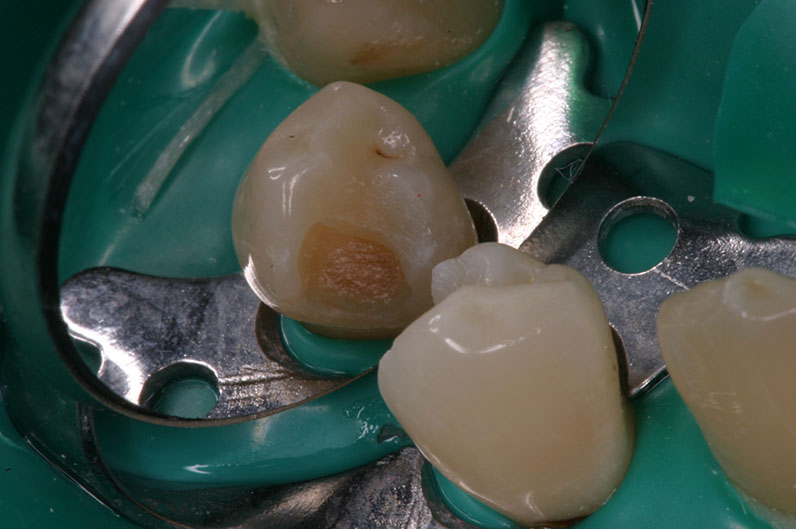

vor Exkavation

mit Proface*

ohne Proface*

nach Exkavation

ohne Proface